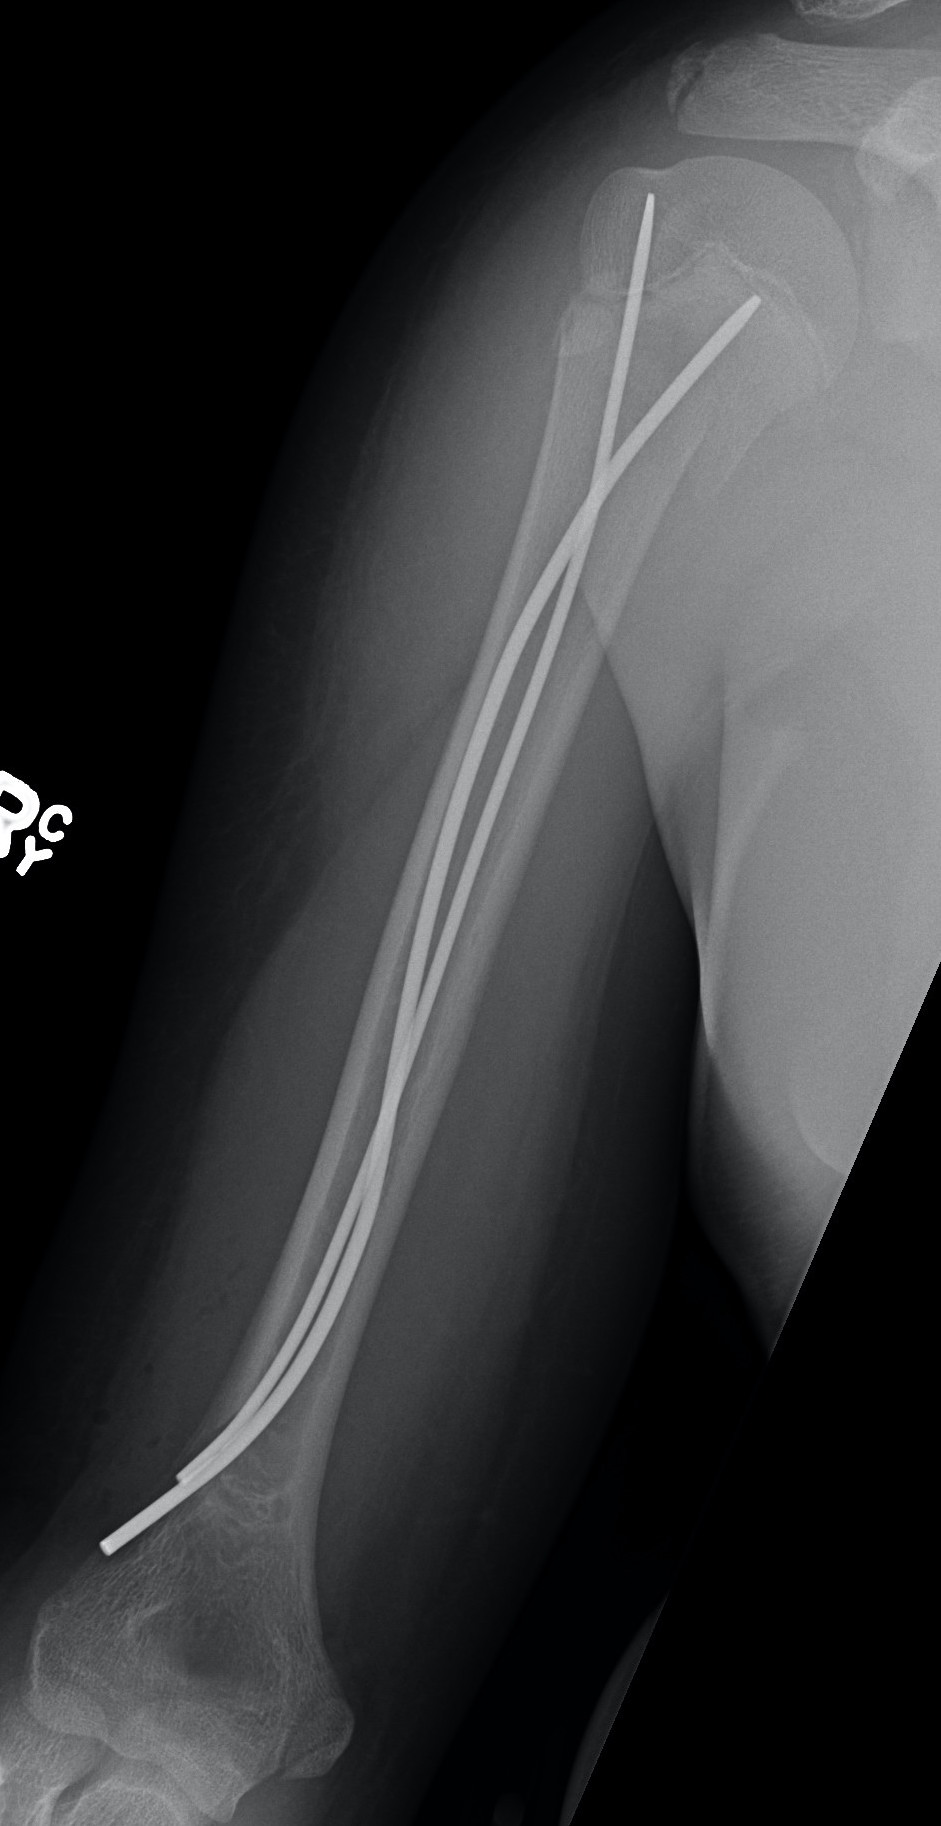

Case: 18 year old boy

Initial xray 18 month xray

- 14 patients average age 10 years treated with retrograde flexible nails

- no loss of position, no growth arrest